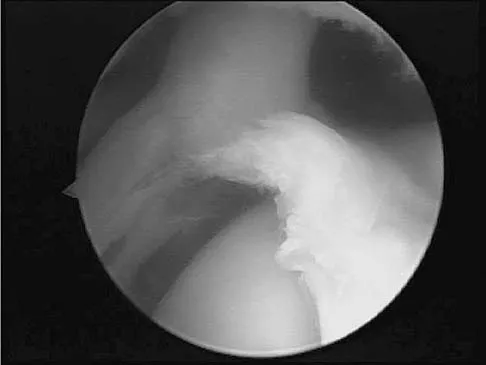

Question 88

A baseball pitcher has intractable posterior and superior shoulder pain. The arthroscopic view seen in Figure 25 shows no Bankart or Hill-Sachs lesion and a negative drive-through sign. There are no signs of ligamentous laxity, but active compression and anterior slide tests are positive. Treatment should consist of